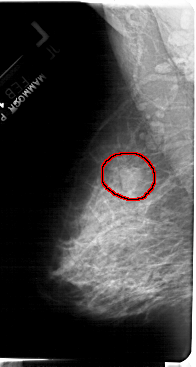

A_1397_1.LEFT_MLO

FILE: A_1397_1.LEFT_MLO.OVERLAY

TOTAL_ABNORMALITIES 1

ABNORMALITY 1

LESION_TYPE MASS SHAPE LOBULATED MARGINS OBSCURED

ASSESSMENT 4

SUBTLETY 3

PATHOLOGY BENIGN

TOTAL_OUTLINES 1

BOUNDARY